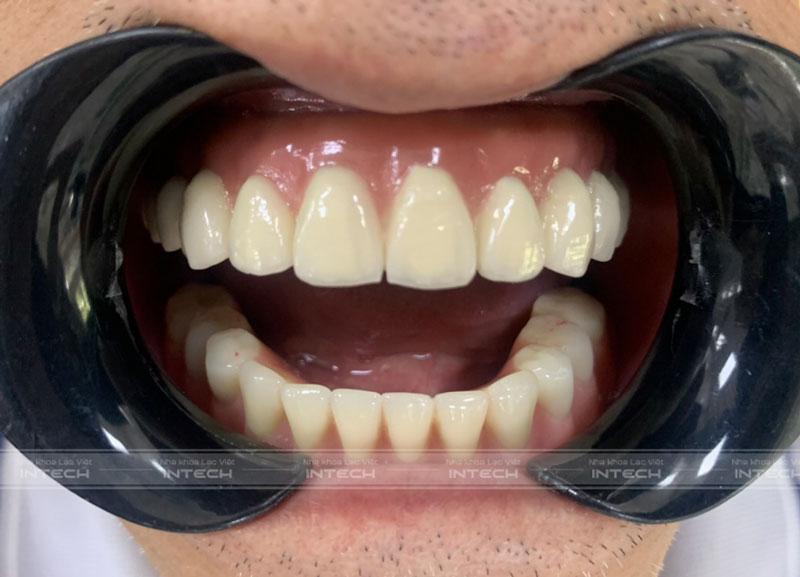

Ảnh cận răng sau khi lắp hàm cố định của chú Vũ Hòa BìnhẢnh cận răng sau khi lắp hàm cố định của chú Vũ Hòa Bình

Sau 3 tháng chờ đợi, cuối cùng chú Vũ Hòa Bình đã được lắp hàm cố định và kết thúc quá trình điều trị. Kết quả sau khi lắp răng khiến chú Bình cảm thấy rất hài lòng.

“Lắp răng xong tôi cảm thấy tự tin hơn hẳn, cảm thấy hai bên má đầy hơn. Từ lúc lắp hàm xong thì ăn uống tốt hơn nhiều và có tăng cân, vì vậy sức khỏe cũng cải thiện tốt hơn.”